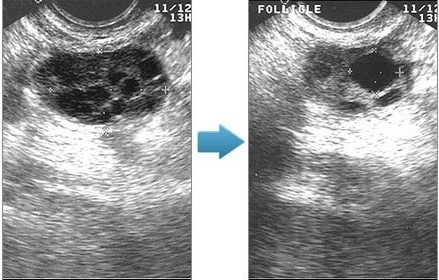

3. 초음파 상에서 다낭성 난소 즉 한개의 난소의 2~9mm직경인 난포가 12개 이상 또는 난소의 용적이 10ml이상

위 그림에서 보시면 정상난소와 다낭성난소의 차이가 확연하게 구별되지요.여자는 태어나면서 100~200만개의 난자를 가지고 태어나구요. 한달에 한번 1개의 난자가 황체난포로 성장해서 배란이 됩니다. 결국 200만개 중 평생 300~400개의 난자만 소진하는 셈입니다. 그런데 다낭성 난소의 경우 정상주기에서 발생하는 되먹이기 기전에 문제가 생긴 경우 여러 개의 작은 낭포가 생기면서 난소 주변에 작은 낭종들이 진주목걸이처럼 배열되어 보이는 초음파 소견을 보입니다

왼쪽이 다낭성 난소, 오른쪽이 정상난소